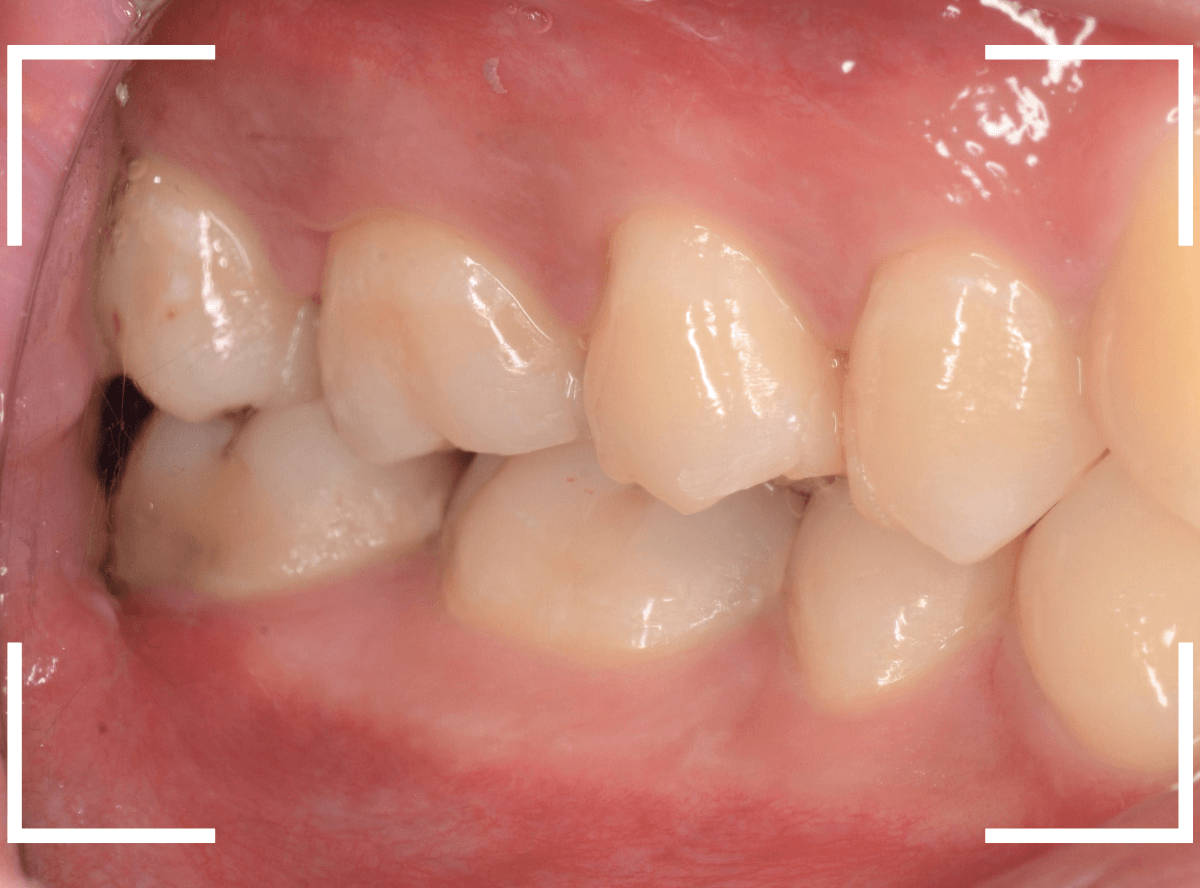

下の奥歯が虫歯になった患者さんのケースです。

〇部が虫歯の部分です。

写真で見てわかるように、常に舌が歯に触っているような状況です。

このような場合、虫歯を見つけづらいですし、治療の難易度もあがります。